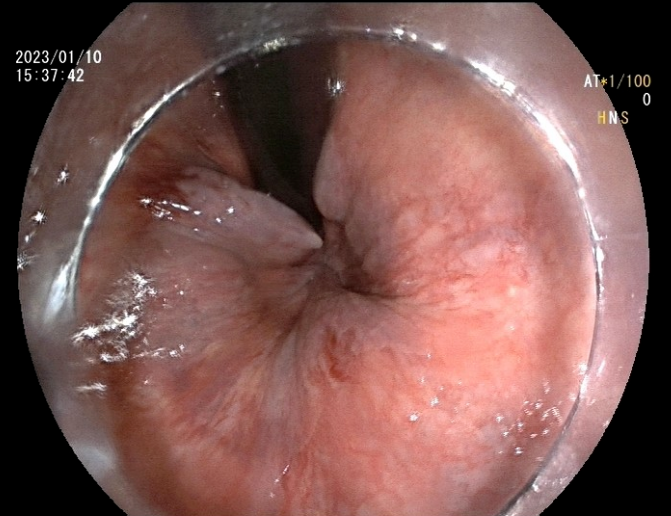

患者李某,男,48岁,主因间断便血2月余,加重20天入院。既往高血压病1级(低危)、高脂血症。患者饱受2个多月间断鲜血便的困扰,且便后伴有异物脱出,门诊以“II期内痔伴出血”收入消化内科。消化内科副主任王铁汉查房时,根据患者目前状况及手术耐受情况,建议其行内镜下内痔硬化剂注射术,并与患者讲解了此术式的优点及相关事项,经过衡量再三,患者同意实施内镜下治疗。

入院的第三天,张芙蓉主治医师在王铁汉副主任的指导下,为患者实施内镜下内痔硬化剂注射术,仅数分钟,手术成功完成。术后患者无任何不适症状,并于三日后出院,术后第7、15天随访,患者表述术后未感觉到任何不适,困扰多月的血便问题得以完美解决。